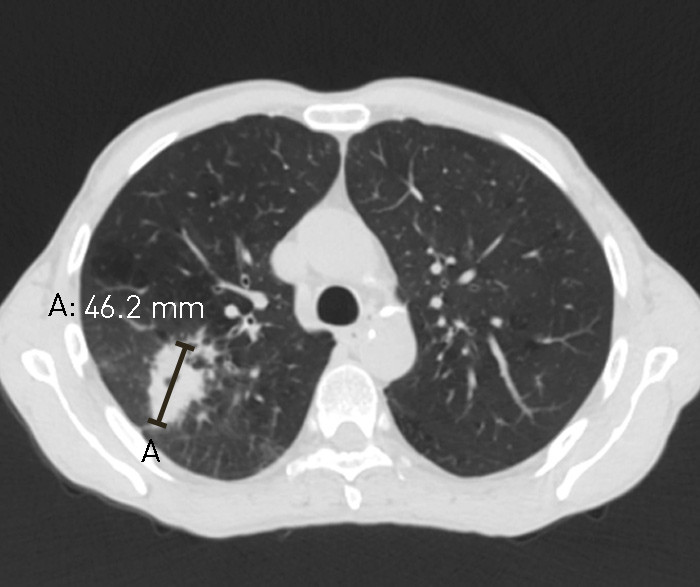

Hos pasienten disse bildene er fra, var svulsten klart synlig og greit tilgjengelig for behandling med stereotaktisk stråleterapi ved første undersøkelse (fig 1). Av ulike grunner gikk det 2,5 måneder før vedkommende kom til behandling og planlegging av stråleterapi med dedikert CT ble gjort (fig 2). Svulsten var da fordoblet i diameter og var størrelsesmessig på grensen for kurerende stråleterapi.

Bildene understreker viktigheten av et raskt utredningsløp og at det motsatte kan influere på pasientens sjanse for kurerende behandling.